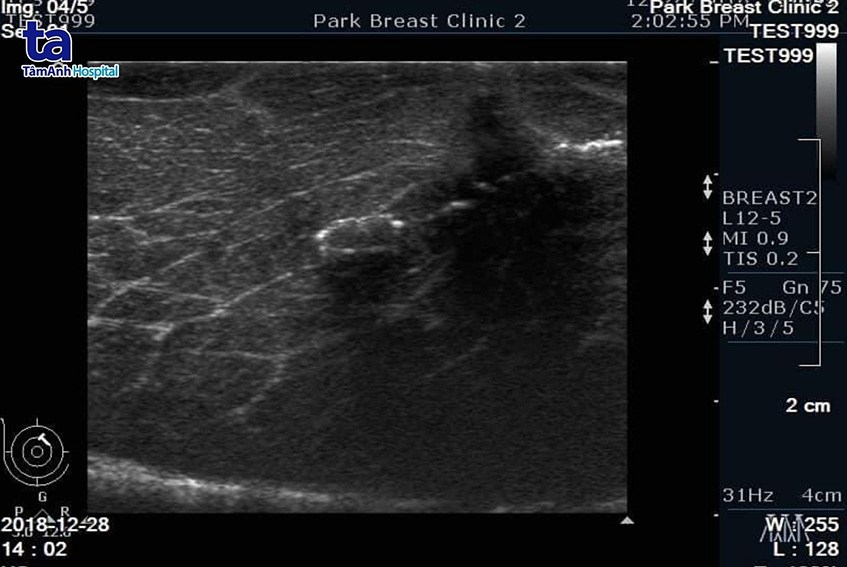

Những điểm đánh dấu nhỏ này có thể quan sát tốt trên siêu âm hoặc phim chụp X-quang, giúp bác sĩ thuận lợi theo dõi, đánh giá xem khu vực u vú trước kia có biến chuyển bất thường nào không qua các lần tái khám.

Marker là một điểm đánh dấu siêu nhỏ với kích thước gần bằng hạt vừng, dạng xoắn, làm từ chất liệu silicon. Nó được đặt vào trong vú sau khi kết thúc thủ thuật sinh thiết u vú, để xác định vị trí nơi khối u đã được lấy ra. Nếu không được đánh dấu, khi mô vú liền lại rất khó để tìm lại vị trí u trước kia để kiểm tra, theo dõi.

Đặc biệt, sau khi hoàn thành VABB, chị còn được bác sĩ đặt thêm một marker vào vị trí khối u vừa được lấy ra. Nếu kết quả xét nghiệm lành tính, marker này giúp đánh dấu vị trí để bác sĩ tiện theo dõi về sau; nếu ác tính, bác sĩ sẽ lấy đây là mốc để phẫu thuật lấy rộng các tổn thương xung quanh. Marker không gây tác dụng phụ với mô sinh học, do đó rất an toàn khi nằm trong cơ thể suốt đời.